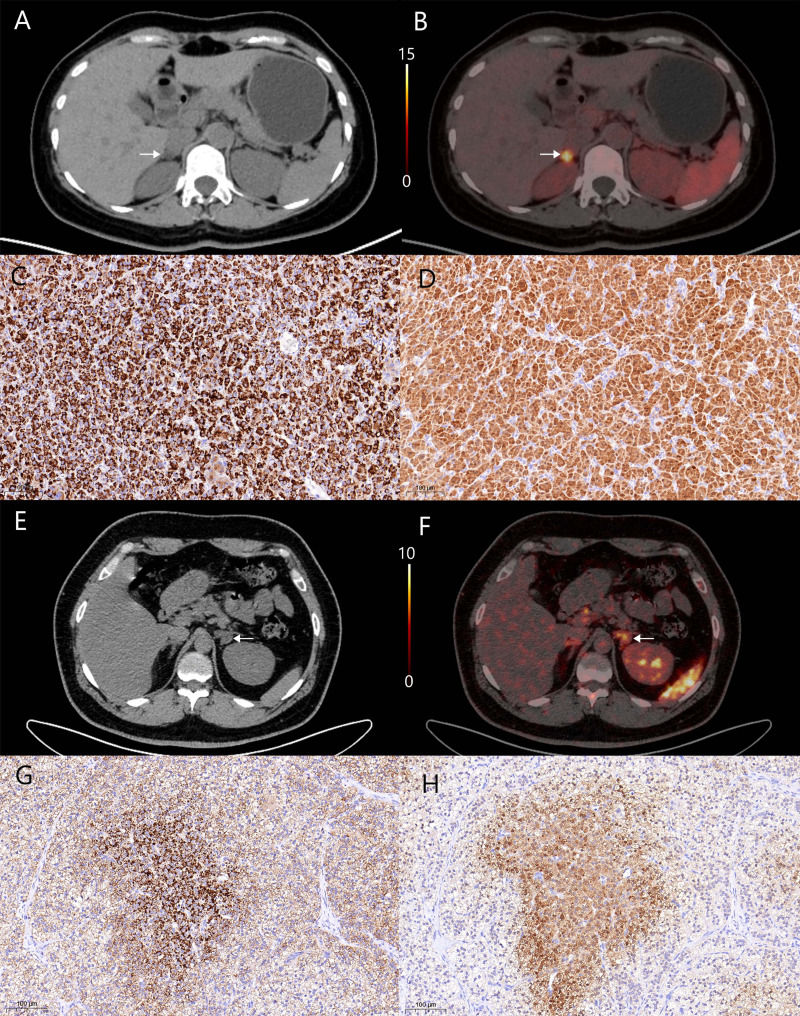

Background: CXCR4 PET/CT imaging has emerged as a tool for diagnosis and subtyping of primary aldosteronism (PA). But its prognostic value for postoperative blood pressure recovery has not been fully discussed.

Results: The lesional SUVmax to the contralateral adrenal tissue SUVmean ratio (LCR) was identified as an independent predictor of clinical success at both the 3-month and 6-month assessments. The AUC for LCR was 0.894 at the 3-month and 0.832 at the 6-month. Patients were divided into high and low LCR groups according to the optimal cut-off of 3.240. The high LCR group exhibited elevated CXCR4 and CYP11B2 expression, higher PAC level, a greater probability of achieving complete clinical success compared to the low LCR group. Moreover, LCR was correlated with lateralization index and contralateral suppression index.

Conclusions: LCR is a reliable independent predictor of postoperative blood pressure recovery in PA. Patients with LCR over 3.240 may benefit more from adrenalectomy. We recommend increased utilization of CXCR4 PET/CT for patients with PA.